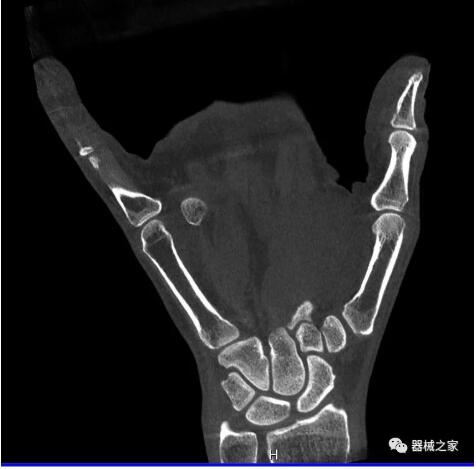

比如上面這款專用于足部和踝部掃查的CT成像系統(tǒng),患者在進(jìn)行CT掃查時只需要站在上面即可,雙腳站或者單腳站都可以,當(dāng)然,如果患者不是那么方便站著做完CT掃查,也可坐在上面。

而患者站著做足部或者踝部做CT檢查還有個好處是,可以檢查患者在負(fù)重的情況下,骨關(guān)節(jié)的真實(shí)情況,而躺著做CT掃查時未必能看出來。負(fù)重CT掃查特別是對于受傷的運(yùn)動員或者舞蹈員來說意義更大,能夠更準(zhǔn)確地評估傷情,幫助他們盡早復(fù)原。

以上介紹的CT均來自國外同一家公司,這些CT均配置了可視化軟件,可以進(jìn)行切片、3D重建以及大型CT附帶的所有典型的操作功能。

以下是這些“特立獨(dú)行”的CT所拍出來的圖像: